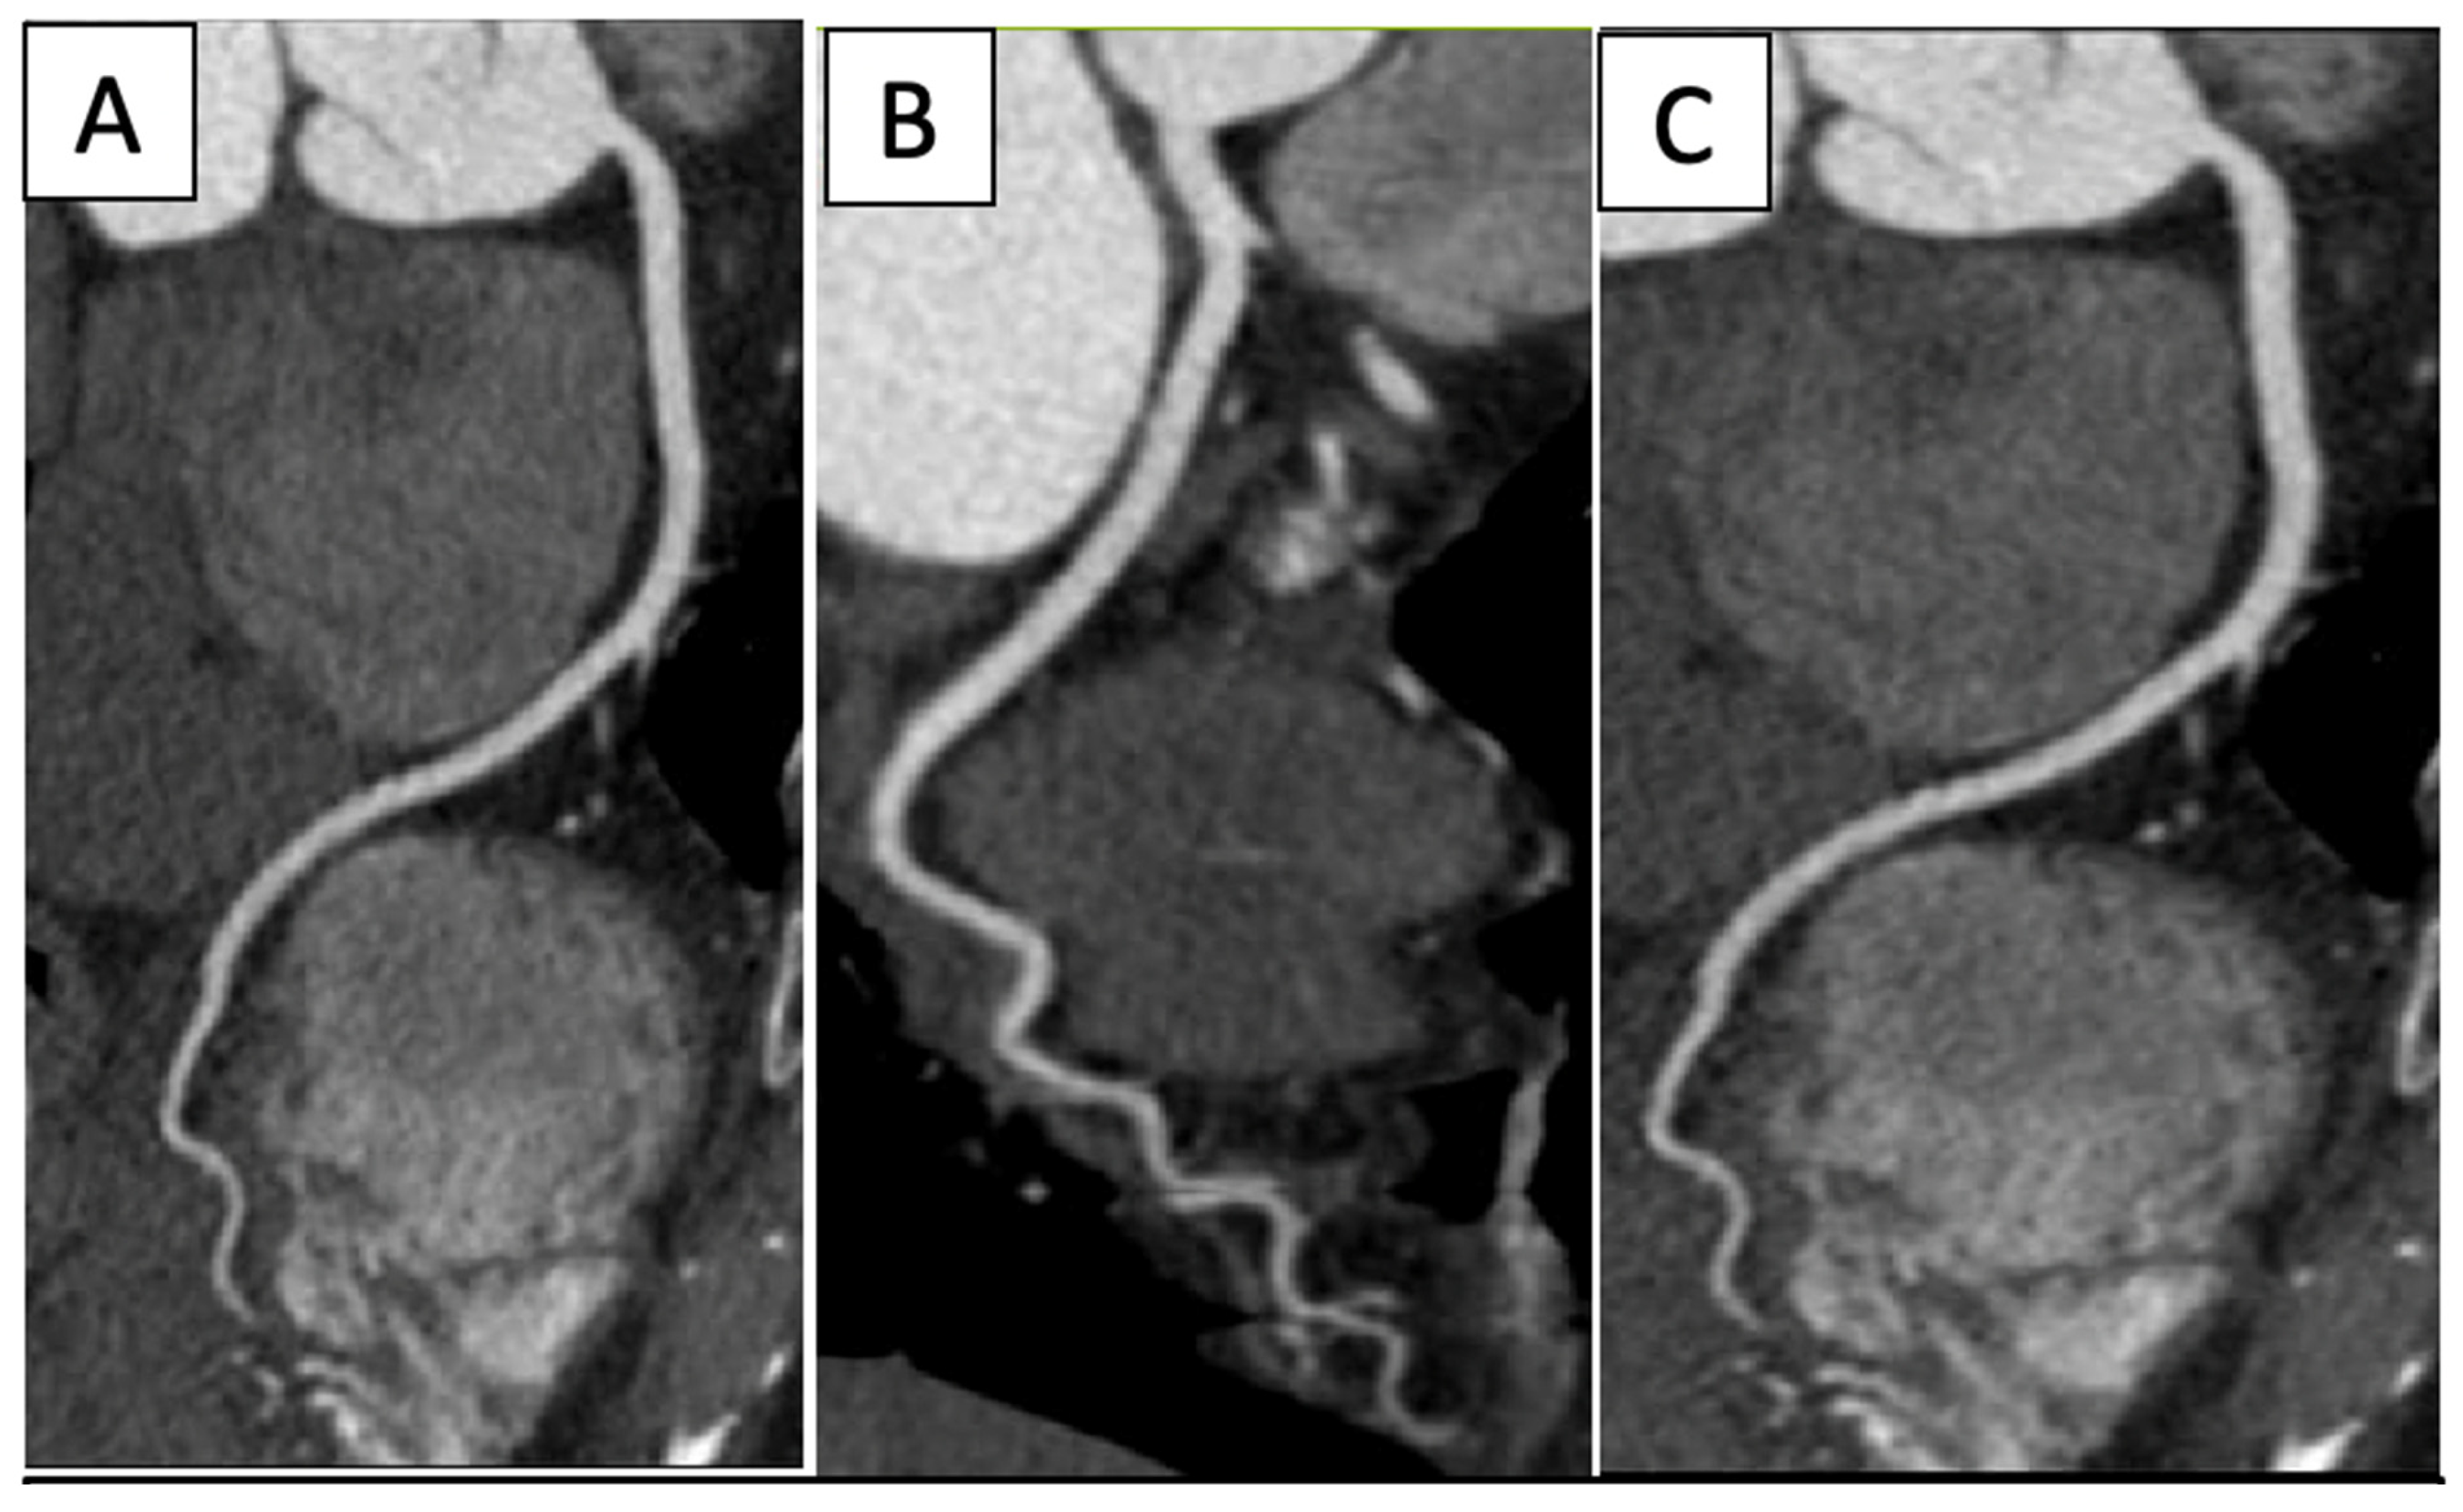

| Nuclear | ![]() | Normal fluorodeoxyglucose uptake in the myocardium |